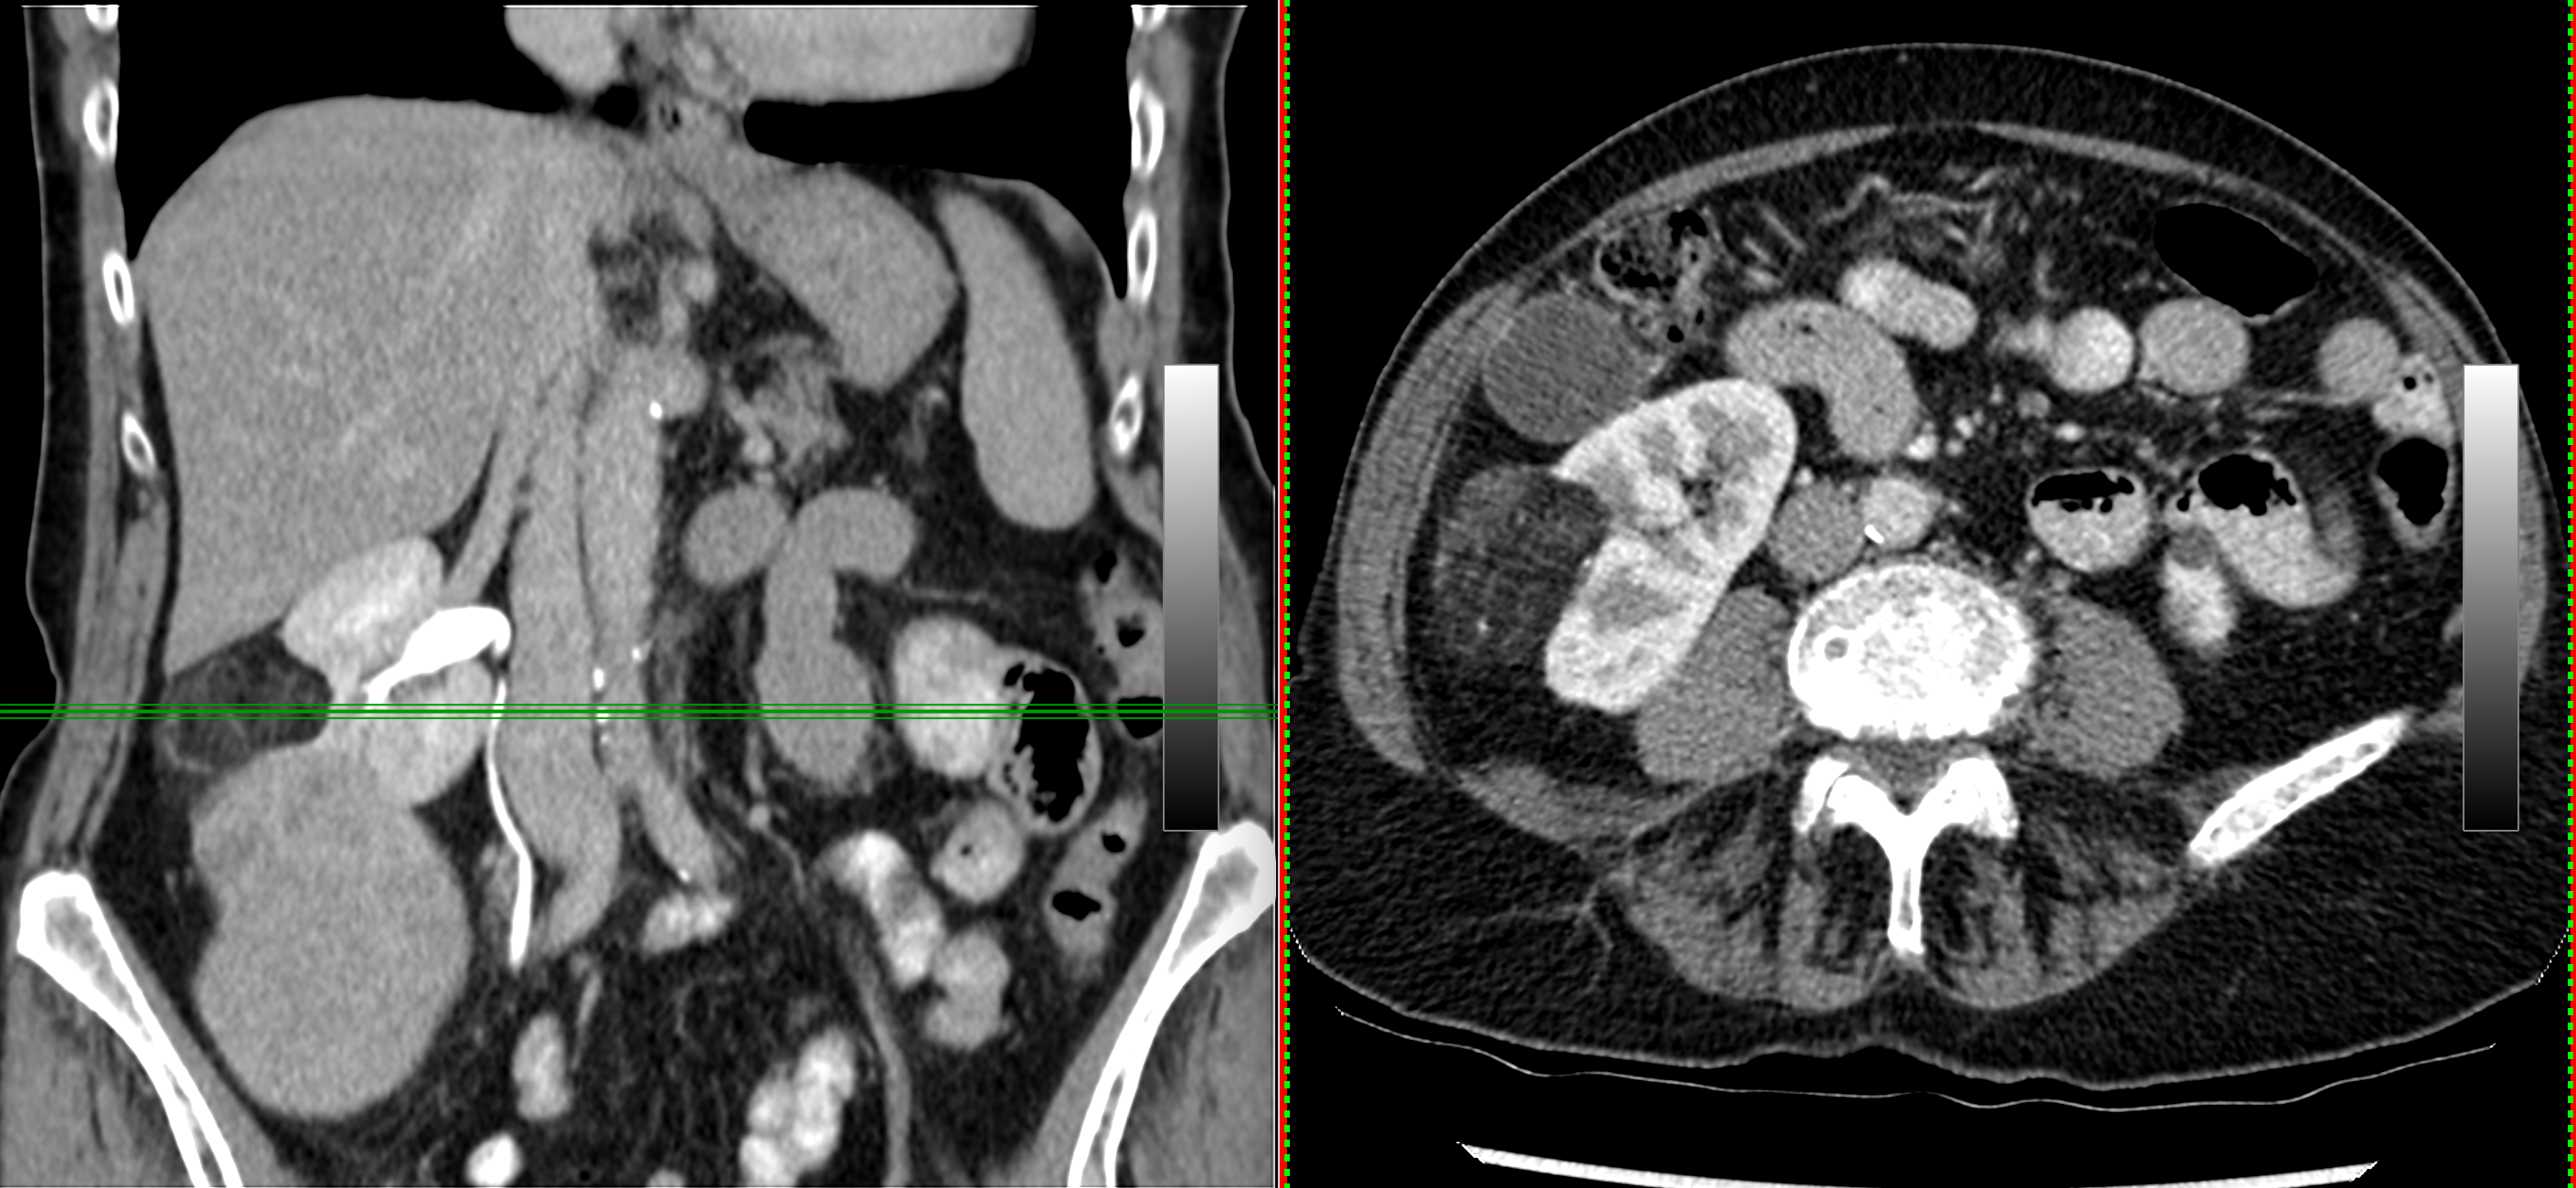

3. Right Kidney Masses - fatty and solid. Angiomyolipoma with coexisting renal cell carcinoma